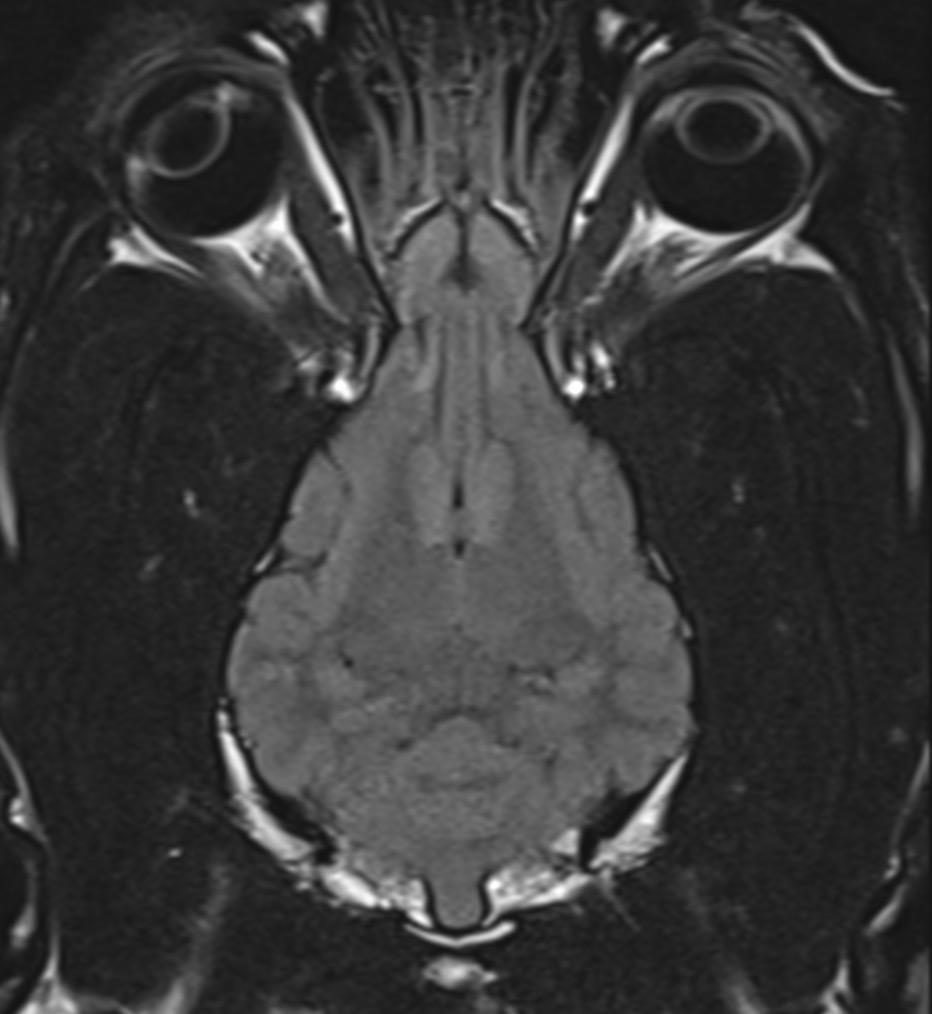

Le service d’imagerie médicale de la clinique vétérinaire Alliance est composé de 2 spécialistes, les Drs vétérinaire Anaïs COMBES et Jade RENARD, toutes deux diplômées du Collège Européen d’Imagerie Médicale Vétérinaire (ECVDI). Elles réalisent chaque semaine et interprètent immédiatement sur site des examens d’IRM de chiens et de chats. Nous utilisons une machine d’IRM haut champ (1,5 Tesla), rapide et très performante. Nous vous proposons des IRM de cerveau, de colonne vertébrale, d’épaule et de grasset (genou) à Bordeaux.

Quel est le principe de l’Imagerie par Résonance Magnétique ? L’IRM permet de capturer des images en 3D d’une partie du corps sans utiliser de rayons X comme le scanner ou la radiographie. La machine contient un puissant aimant, un système émetteur-récepteur de radiofréquence, ainsi qu’un ordinateur de calcul ultra-performant. L’examen IRM permet avec une très bonne précision de distinguer l’anatomie fine de l’animal, de préciser la nature des tissus observés et donc de diagnostiquer de nombreuses maladies qui ne seraient pas visible avec d’autres modalités d’imagerie.

Les principales indications de l’IRM sont des crises convulsives, des signes nerveux comme l’ataxie, le syndrome vestibulaire, la paralysie faciale, la perte de vision, le changement de comportement, la paralysie, une faiblesse postérieure, une incontinence urinaire ou fécale, une dorsalgie, un torticolis, une otite chronique, une masse ou une boiterie identifiée comme provenant de l’épaule ou du grasset.